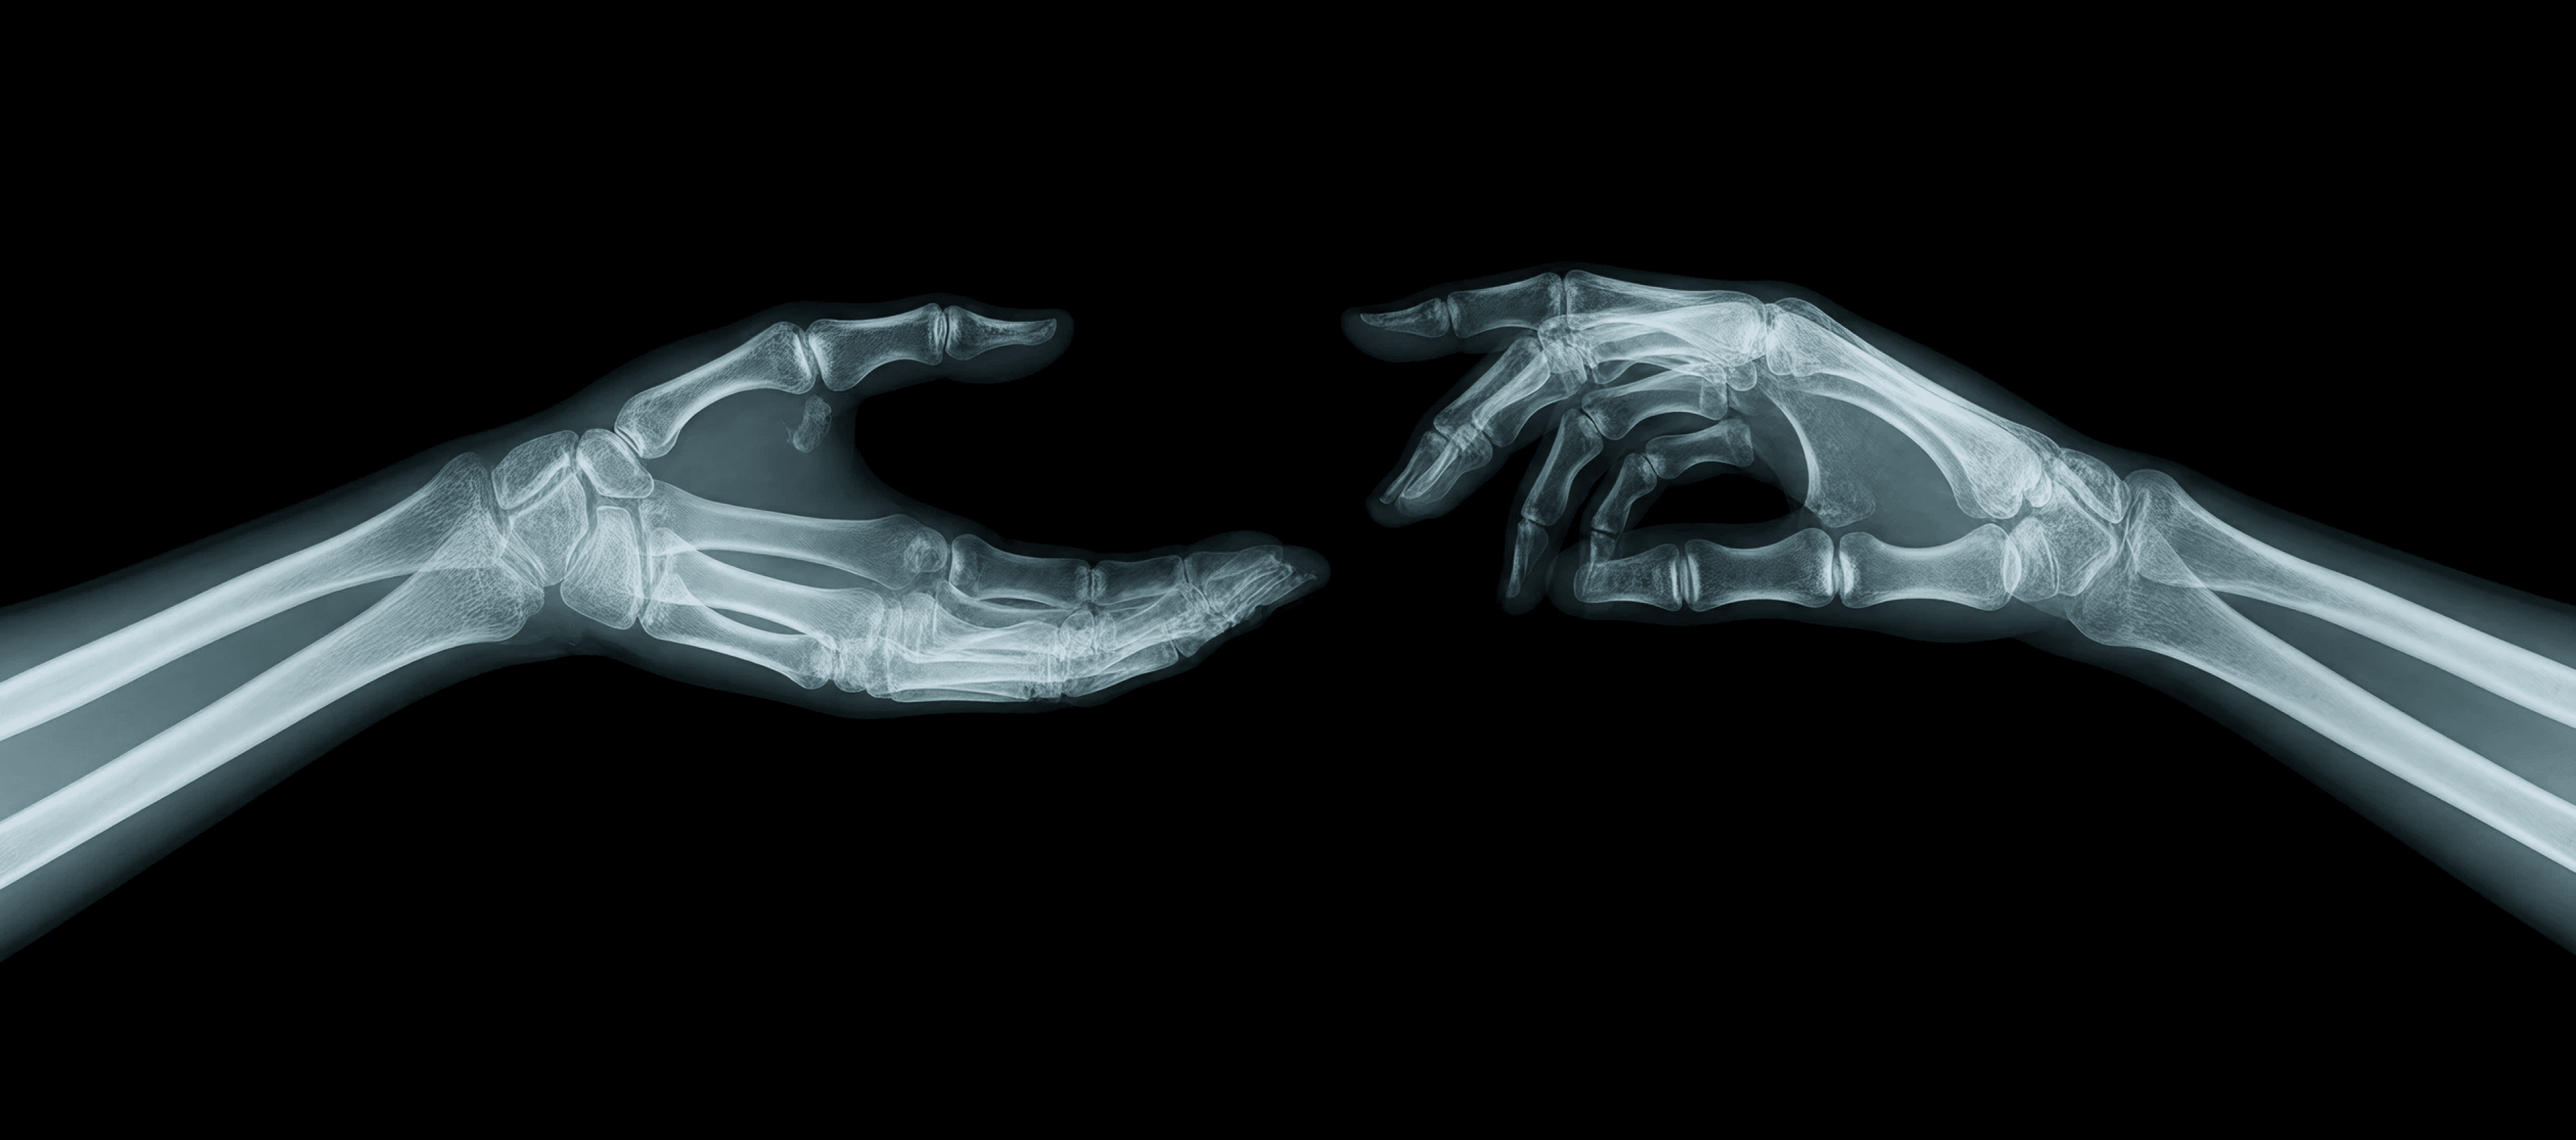

Spinal X-ray

High-resolution scans of the cervical, thoracic, and lumbar spine to evaluate alignment, disc spacing, and structural integrity